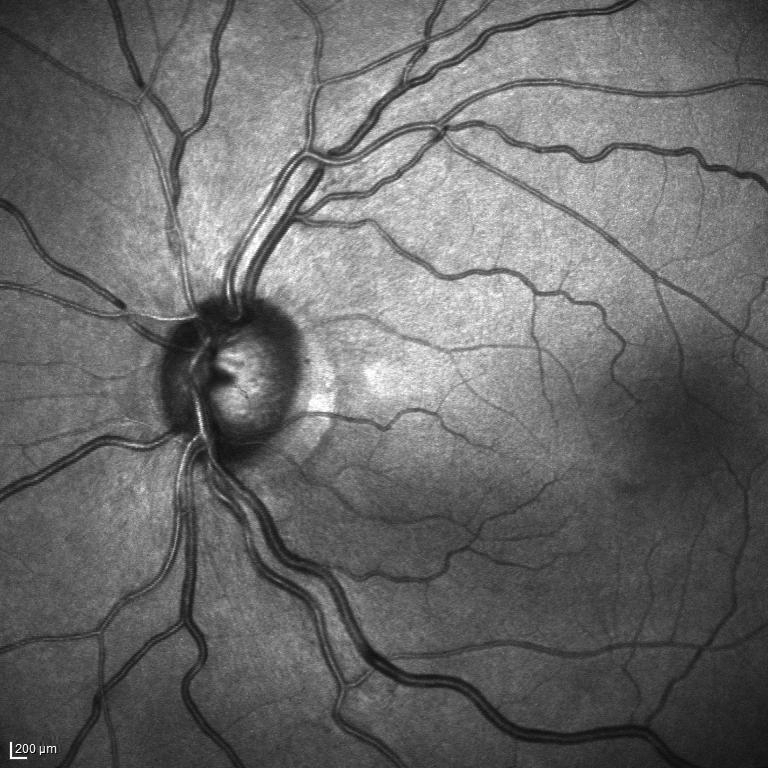

III The RAVIR Dataset

Recently there has been a substantial increase in the utilization of single wavelength confocal imaging that only captures reflected light passing through a pinhole, which will allow capturing high quality, high contrast fundus images. The images in our RAVIR dataset were captured using infrared (815nm) Scanning Laser Ophthalmoscopy (SLO), which in addition to having higher quality and contrast, is more convenient for the patient and is less affected by opacities in optical media and pupil size. This imaging modality is also commonly used in ophthalmology clinics. The RAVIR dataset consists of 46 IR retinal images from the UCLA Stein Eye Institute imaging database, divided into train and test sets of 26 and 20 images, respectively. We used 4 images from the 26 test images as our validation set. The images were captured using a Heidelberg Spectralis camera with a FOV. They are sized at pixels and compressed in the Portable Network Graphics (PNG) format. Each pixel in the images has a reference length of 12.5 microns. Table I compares our RAVIR dataset against other retinal vessel segmentation datasets.

Manual pixel-wise annotations were performed and verified by our experienced retinal image analysis specialist. Per-pixel labels were applied to all vessel regions that could accurately be identified as artery or vein. Vessels were labeled over the ONH in those images where the arteries and veins could be resolved. However, for images in which the veins and arteries over the ONH were indistinguishable, the ONH region was blocked for masking.